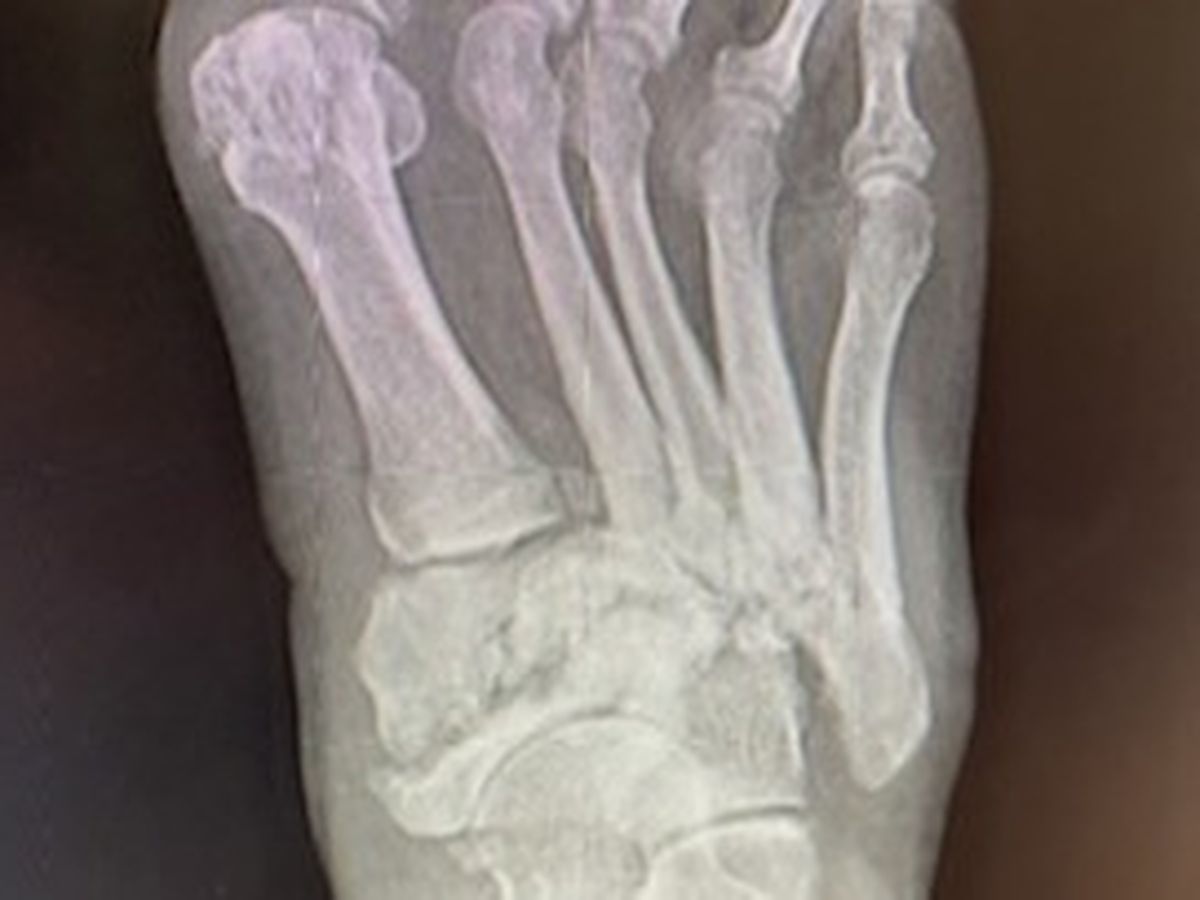

Unfortunately, I’ve become disabled and can no longer work at all. Over the last several years, I’ve lost all the toes on my left foot and had a heart attack, quadruple bypass and knee replacement. Now I’ve been diagnosed with a condition called Charcot Foot, and I need my right leg amputated below the knee. The condition was caused by years of inflammation and infection resulting from Diabetes.